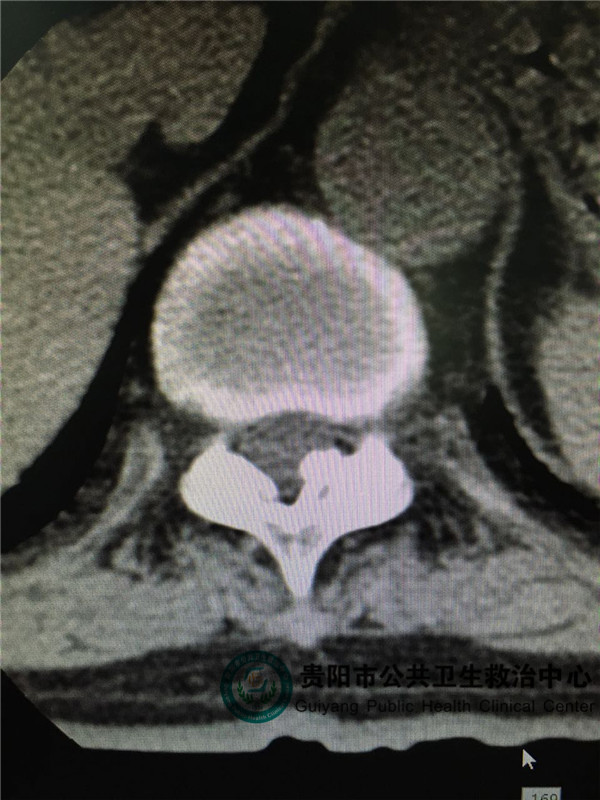

圖2

圖2,圖3,圖4是胸椎病灶節(jié)段CT平掃,可見(jiàn)椎管左側(cè)有占位壓迫脊髓,椎管明顯變窄。和患者體征相符。